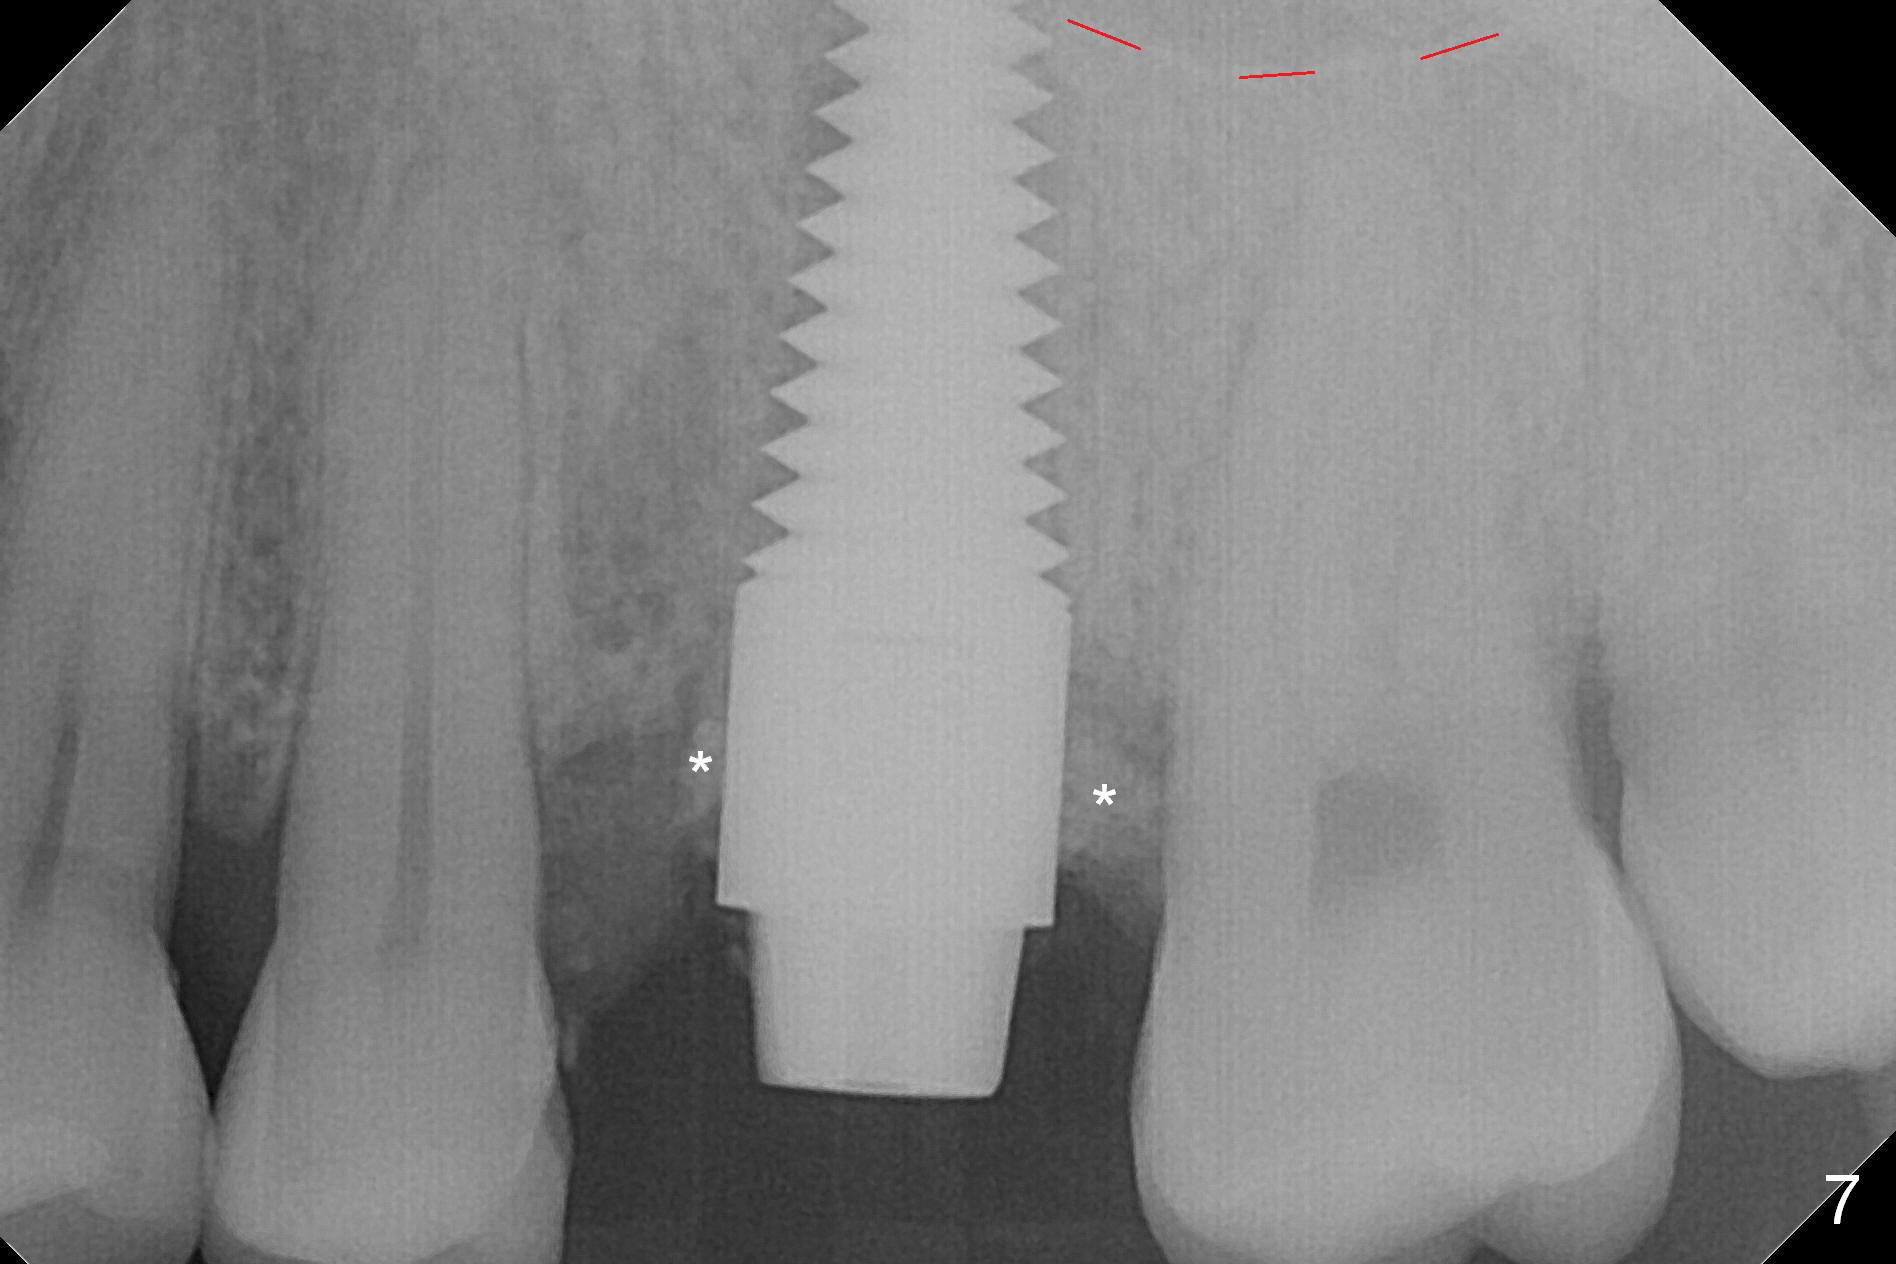

The septum perforates into the distobuccal socket when 4.3 mm drill is being used. The sinus floor bone (Fig.5 *, Fig.6-8 red dashed line) has to be used for primary stability. Finally a 6x20 mm tap achieves stability apparently by engaging to the mesial and distal walls of the socket (Fig.6). The insertion torque of a 6x20 mm tissue-level implant is > 60 Ncm (Fig.7) with allograft packed into the remaining socket (*).

A much smaller implant should be used (e.g.4.5 mm) in order to save the septum. But the apical granulation tissue above the septum cannot be removed completely. There is no bone loss around the implant 4 months postop (Fig.9), although the gingiva is unhealthy because of lack of oral hygiene locally. The immediate provisional is not reseated with oral hygiene instruction. Impression will be taken in 2 weeks. Take photos to show disappearance of the fistula.